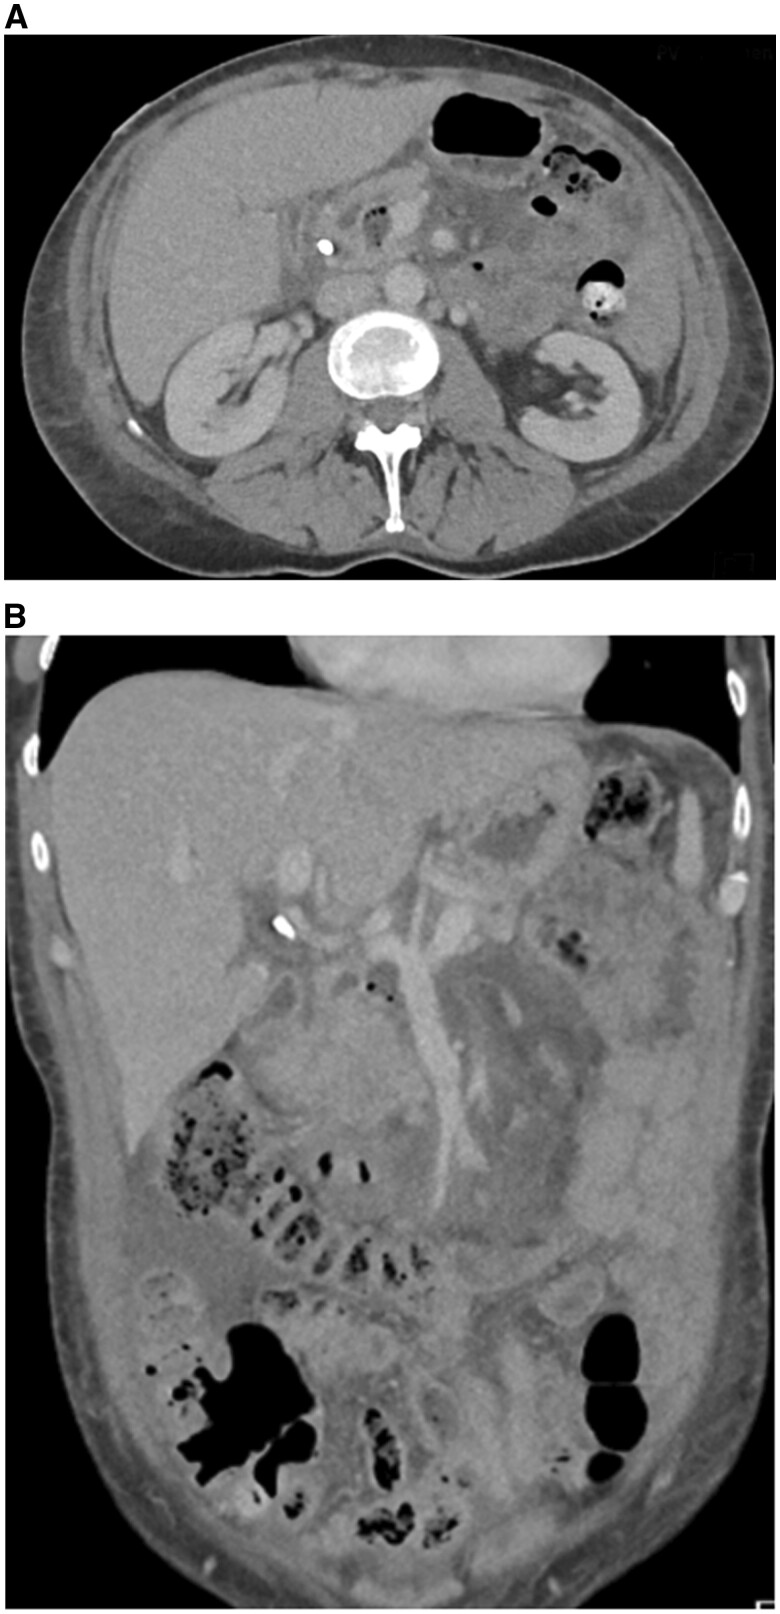

严重胰腺炎后逆行胆管造影(ERCP)是罕见的发生。更罕见的是,在ercp诱导的胰腺炎后可能出现的其他非胰腺症状,如胰腺炎和多发性关节炎。这种症状的组合被认为是胰腺炎、胰膜炎和多关节炎综合征(PPPS)。PPPS典型表现为红色皮下结节,主要发生在下肢。在某些情况下,病情可能进展到骨骼,引起髓内脂肪坏死/骨梗死。关节并发症包括多关节炎,影响大小关节。PPPS往往发生在临床胰腺炎高峰后3-6周。在本报告中,我们提出了一例PPPS作为ERCP后并发症发生的病例。由于菌血症和真菌血症的存在,这一特殊病例进一步复杂化,导致随后发展为多灶性骨髓炎。本报告中包含的医学影像提供了整个临床过程的全面概述,从最初的术后并发症和胰腺炎开始,随后使用超声和MRI进行多模态成像,描绘了睫状体炎,最后说明了多灶性骨髓炎的发展。本病例为探讨和了解胰腺炎相关的两种罕见并发症:PPPS和多灶性骨髓炎提供了机会。

Severe pancreatitis following retrograde cholangiopancreatography (ERCP) is an infrequent occurrence. Even rarer are the additional non-pancreatic symptoms that can emerge after ERCP-induced pancreatitis, such as panniculitis and polyarthritis. This combination of symptoms is recognized as the pancreatitis, panniculitis, and polyarthritis syndrome (PPPS). PPPS typically manifests as reddish subcutaneous nodules, primarily in the lower extremities. In some cases, the condition may progress into the bones, causing intramedullary fat necrosis/bone infarcts. Joint complications involve polyarthritis and affect both small and large joints. PPPS tends to develop 3-6 weeks after the peak of clinical pancreatitis. In this report, we present a case of PPPS that occurred as a complication following ERCP. This particular case became further complicated by the presence of bacteraemia and fungaemia, leading to the subsequent development of multi-focal osteomyelitis. The medical imaging included in this report provides a comprehensive overview of the entire clinical course, starting from the initial post-procedural complication and pancreatitis, followed by multi-modal imaging depicting panniculitis using ultrasound and MRI, and finally illustrating the development of multi-focal osteomyelitis. This case serves as an opportunity to explore and understand 2 rare complications associated with pancreatitis: PPPS and multi-focal osteomyelitis.